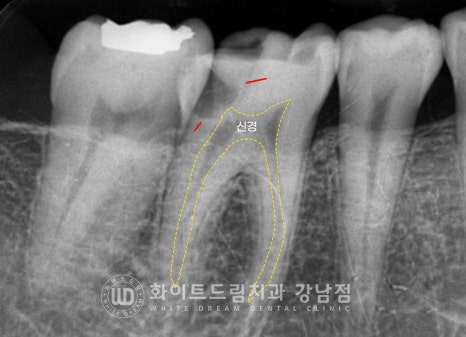

▲ 46번 인레이가 떨어진 치아 부위, 신경이 겉으로 노출되어 있는 상태여서 신경치료를

진행하게 되었습니다.

신경치료는 치아 안쪽에 위치한 신경을 제거하는 치료이기에

치아 내부 깊숙이 위치한 신경으로 접근하기 위해 치아 삭제가 동반될 수밖에 없습니다.

보통 이렇게 치아의 외벽만을 남겨두고 치아 내부를 삭제하기 때문에

치아가 굉장히 약해지게 됩니다.